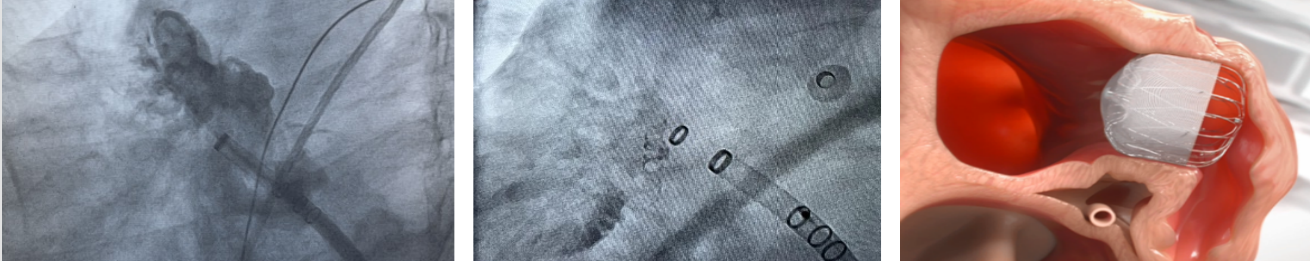

手术将“左心耳封堵”与“房颤射频消融”融为一体,在通过射频消融帮助患者恢复正常心跳的同时,封堵左心耳这个血栓根源,将发生血栓栓塞的风险降至最低,从而防止卒中风险。

电生理团队首先采用CARTO 3三维标测系统成功为患者实施射频消融术,随后,进行左心耳封堵术。

三维标测系统的引导,快速成像、精准定位、准确消融,不仅提高了手术效果,而且也减少了术中发生严重并发症的几率。

左心耳封堵术是一种出血量极小的、安全的微创操作,通过一根4毫米的传输装置将事先准备好的封堵器置入左心耳口部,经过评估后释放封堵器,左心耳开口就被“封堵”住了。

整个手术时间短、创伤小。不需开胸,时间为20-30分钟,过程中患者不会有特殊的不适感,术后房颤患者恢复快,仅需要服用抗凝药数月,待封堵器被心内组织完全覆盖后,即可告别长期服用抗凝药的烦恼,同时有效降低了脑中风的发生率。